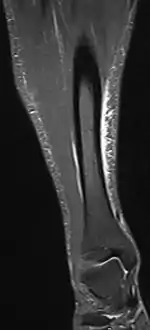

Other potential causes include stress fractures, compartment syndrome, nerve entrapment, and popliteal artery entrapment syndrome.[18] If the cause is unclear, medical imaging such as a bone scan or magnetic resonance imaging (MRI) may be performed.[3] Bone scans and MRI can differentiate between stress fractures and shin splints.[12]